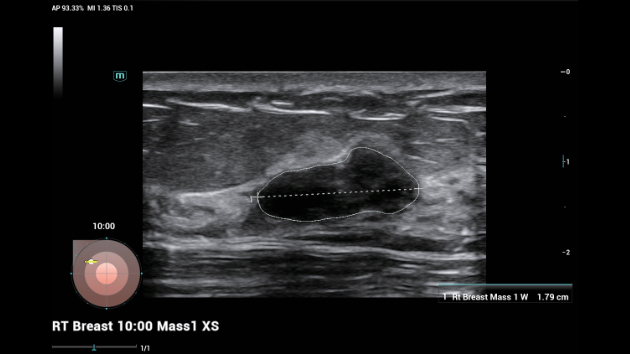

Soluzioni di diagnostica per immagini complete con tecnologia ZST+

La piattaforma ZST+ è un'innovazione straordinaria, che rappresenta un'evoluzione nel campo dell'ecografia. Grazie alla trasformazione delle metriche a ultrasuoni dal beamforming convenzionale all'elaborazione basata sui dati di canale, supera la tradizionale limitazione del trade-off tra risoluzione spaziale, risoluzione temporale e uniformità dei tessuti, offrendo una qualità d'immagine eccezionale per infinite soluzioni di imaging con miglioramenti continui.